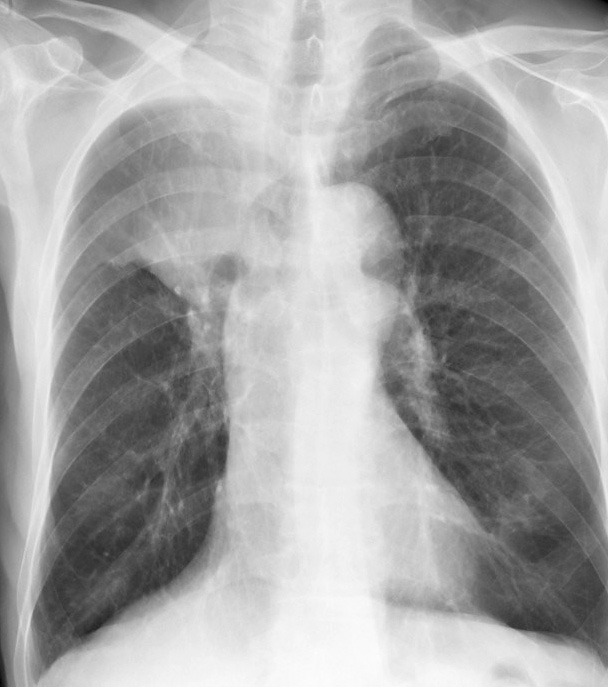

RUL Collapse Case 3 PA